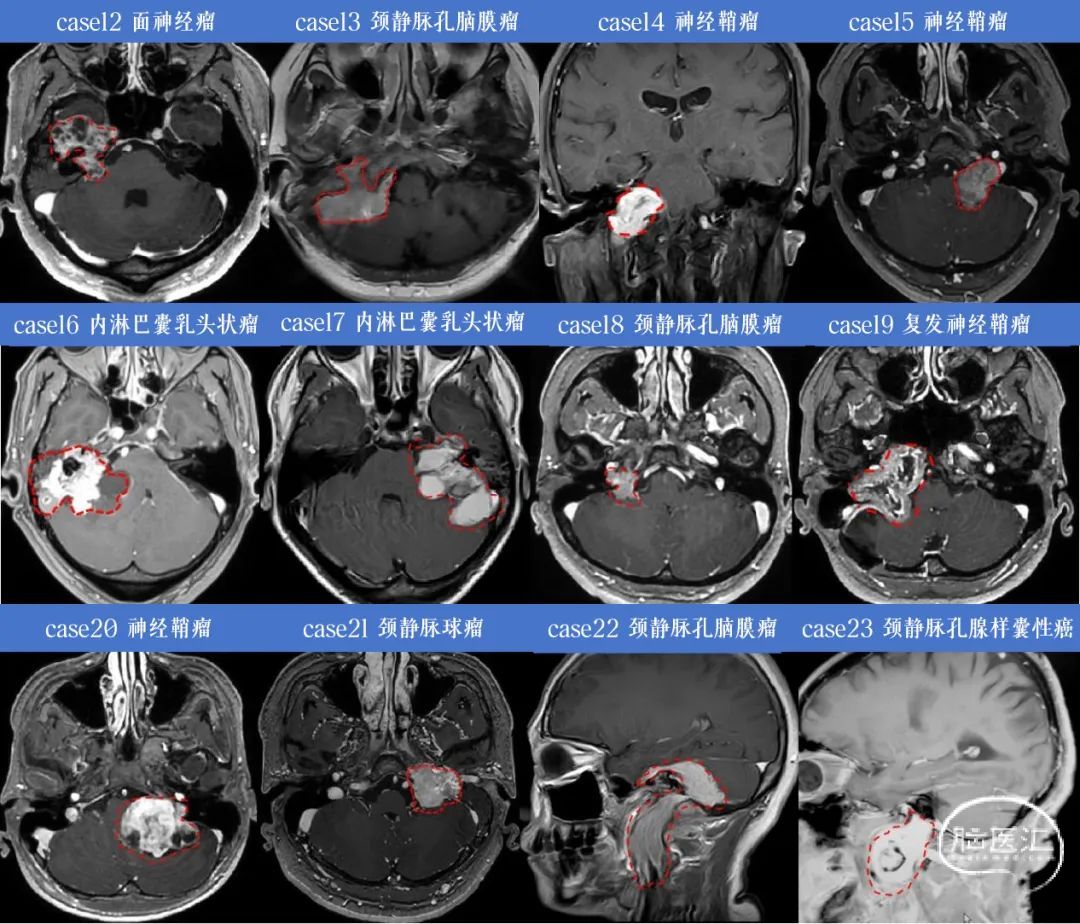

2024年术者在首都医科大学三博脑科医院院内外共手术治疗岩骨及颈静脉孔区肿瘤23例,神经鞘瘤11例(包括面神经瘤2例,舌下神经鞘瘤1例),脑膜瘤5例,颈静脉球瘤3例,内淋巴乳头状腺瘤2例,软骨肉瘤1例,腺样囊性癌1例。23例中岩枕入路7例,迷路下入路6例,乙状窦后入路4例,颞下窝入路3例,远外侧入路1例,颞下联合迷路下入路1例,颈部切口入路1例。

图2. 病例12-23术前核磁共振影像